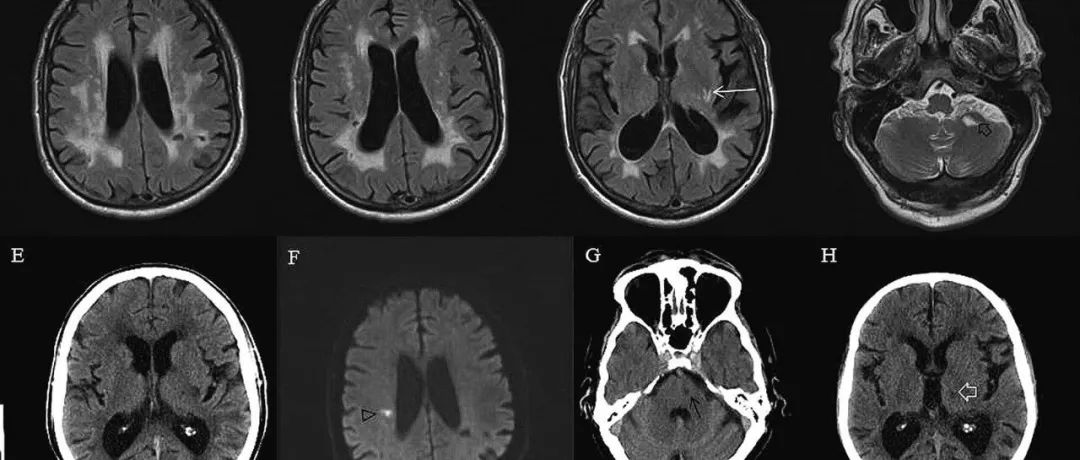

专家述评:血管性帕金森征群

血管性帕金森征群(vascular parkinsonism)是指某些脑血管病引起的中枢神经系统进行性变性疾病,主要累及纹状体-黑质结构及其投射到丘脑-皮质神经纤维、神经结构,产生少动-强直症状群、震颤、步态障碍、下半身综合征(lower body syndrome)等临床表现的变性疾病。01血管性帕金森征群的流行病学的研究血管性帕金森征群的流行病学研究报道很多,各家报道不一,但无肯定的流行率(表1)。...